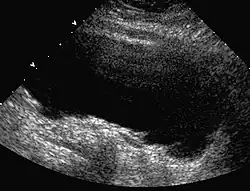

Ein wichtiges Zeichen in der Bildgebung ist die Blasenwandverdickung, insbesondere eine Trabekulierung (unregelmäßige Zähnelung) der Wand. Zur weiteren Abklärung stehen sonografische Restharnbestimmung, Urodynamische Untersuchungen, MCU zur Verfügung.[2]